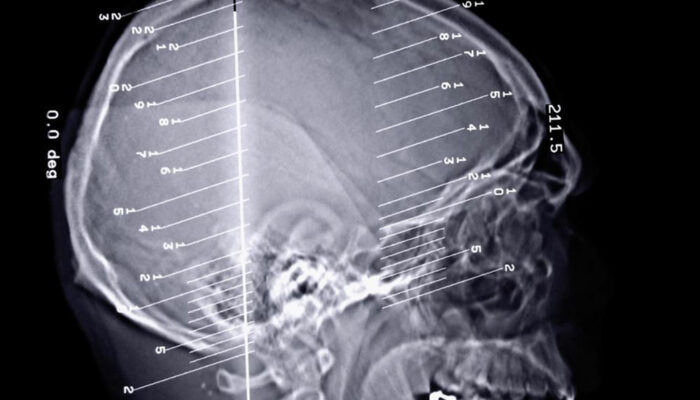

Epilepsy is a dreaded disorder, especially since it is connected to the dysfunctioning of the brain. The brain plays a pivotal role in the functioning of the human body and any kind of issue can lead to severe complications. The disorder is related to the dysfunctioning of the central nervous system in the brain.